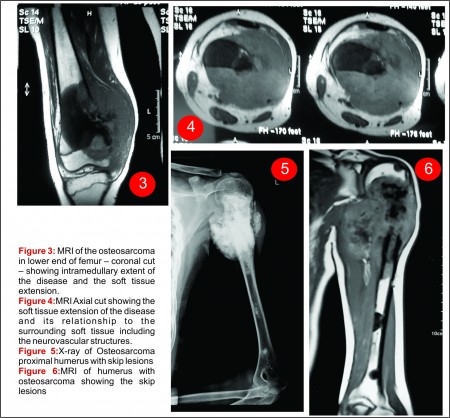

Современные методы диагностики включают рентгенографию, компьютерную томографию, которая позволяет определить объем поражения кости, близлежащих мягких тканей, обнаружить метастазы в легких.

Магнитно-резонансная томография дает возможность наиболее подробно изучить мягкие ткани и костный мозг. С помощью МРТ нередко удается выявить самые мелкие локализации остеогенной саркомы, что особенно важно для благоприятного прогноза заболевания.

При диагностике остеосаркомы собак поражающей скелет, первым методом обследования является качественное радиографическое обследование животного.

Общие отклонения на снимках при остеосаркоме заключаются в почти полном лизисе кости в зоне поражения совместно с остеобластическими и остеокластическими изменениями различной степени выраженности на периферии. Радиографическими особенностями остеосаркомы кости являются выраженный лизис кортикального слоя (вплоть до патологических переломов), формирование новой кости вокруг опухоли (типа вспышки солнца) с приподнятием надкостницы и значительное увеличение объема окружающих мягких тканей. На ранних этапах развития опухоли, радиографические изменения могут заключаться в потере ясного трабекуллярного паттерна метафиза и размытии переходной зоны в месте локализации опухоли. Радиографические изменения остеосаркомы собак зависят от размера, гистологического подтипа, локализации и времени развития опухоли. Радиографические признаки остеосаркомы сходны с таковыми при остеомиелите, особенно грибковом. Радиографические изменения при остеосаркоме кошек сходны с таковыми при остеосаркоме собак.

вторичные метастатические опухоли костей). Метастазы остеосаркомы в легких не определяются радиографически пока не достигают размера 6-8 мм в диаметре. В обследовании животного с остеосаркомой могут играть роли более современные методы визуального исследования (пр. КТ, МРТ, ядерная сцинтиграфия), но современные требования к стадированию опухоли и лечению, все же основываются на данных радиографического обследования.